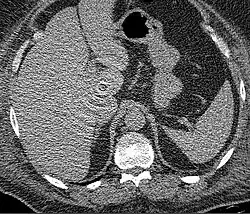

The acquisition of dual-energy data proves useful in clinical applications such as detecting uric acid versus calcium kidney stones, characterizing pulmonary embolism with iodine maps, and improving lesion conspicuity in liver imaging through virtual non-contrast and material decomposition.